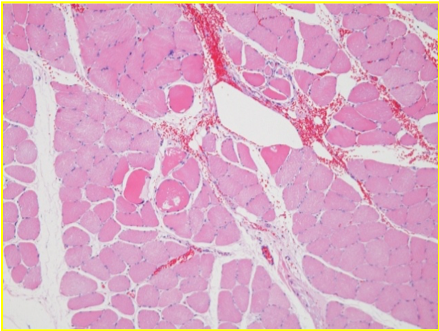

дезорганізація спостерігається через 25 хв після Ендопіл

реорганізація через 60 хв після Ендопіл

після ін'єкції 0,05 мл Ендопіл